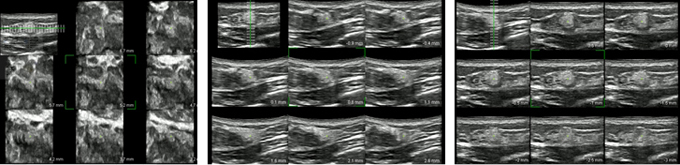

正常乳線の縦断面超音波像を

厚み付き画像で表示

正常乳線の水平面、縦断面、横断面の超音波像をそれぞれ0.5mm間隔のスライスで表示